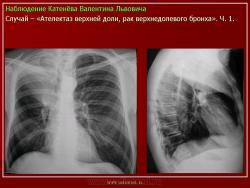

Наблюдения коллег.